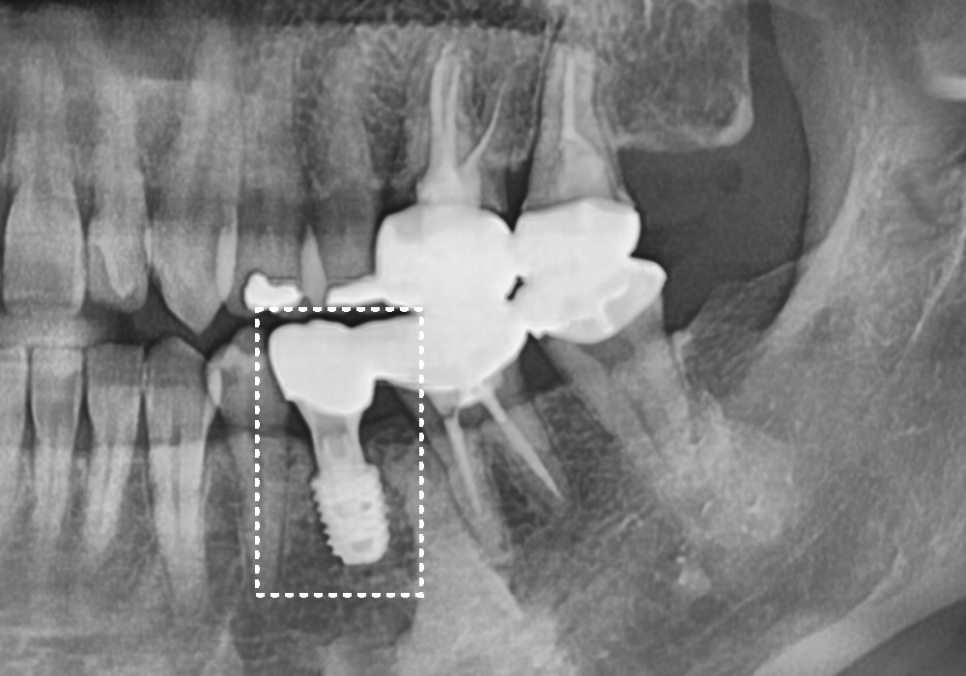

다행히 뿌리 쪽에 염증이 번지지 않은 상태라,

치아를 뽑은 당일에 바로 임플란트를 심는

'발치 즉시 식립'을 진행했습니다.

241108

신경관과 충분한 거리를 두면서

가장 이상적인 위치에 알맞게 심어진 것을

확인할 수 있었죠.